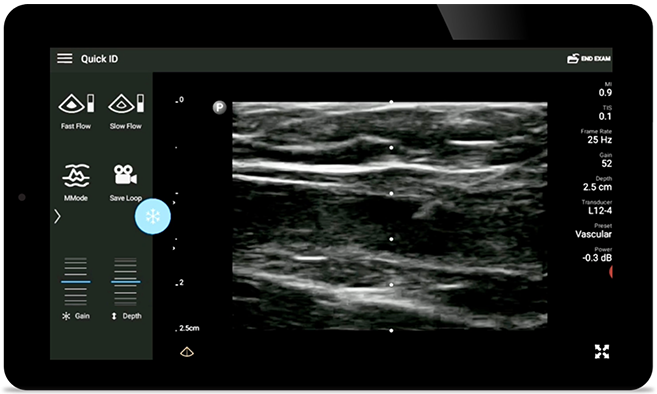

Lumify L12-4 broadband linear array transducer

• 12 to 4 MHz extended operating frequency range

• Aperture size: 34mm

• 2D, steerable color Doppler, M-mode, advanced XRES and multivariate harmonic imaging, SonoCT

• High resolution imaging for shallow applications: soft tissue, vascular, superficial, musculoskeletal, and lung

• Center line marker

• USB-C transducer with replaceable cable